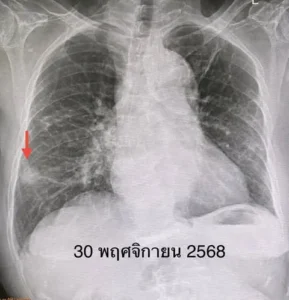

ตรวจร่างกาย ไม่มีไข้ ฟังปอดปกติ เอกซเรย์ปอด มีเงาผิดปกติปอดข้างขวาด้านบนจากเคยป่วยเป็นวัณโรค และมีก้อนขนาด 1.9 × 1.9 เซนติเมตรที่ปอดข้างขวาด้านล่าง ก้อนนี้เป็นก้อนใหม่เพิ่งพบครั้งแรก ปีที่แล้วไม่มีก้อน ทำคอมพิวเตอร์ปอด พบก้อนขนาด 3.0 × 2.4 × 2.0 เซนติเมตรที่ปอดข้างขวาด้านล่าง ตรวจเลือด ค่ามะเร็งทุกตัวปกติ